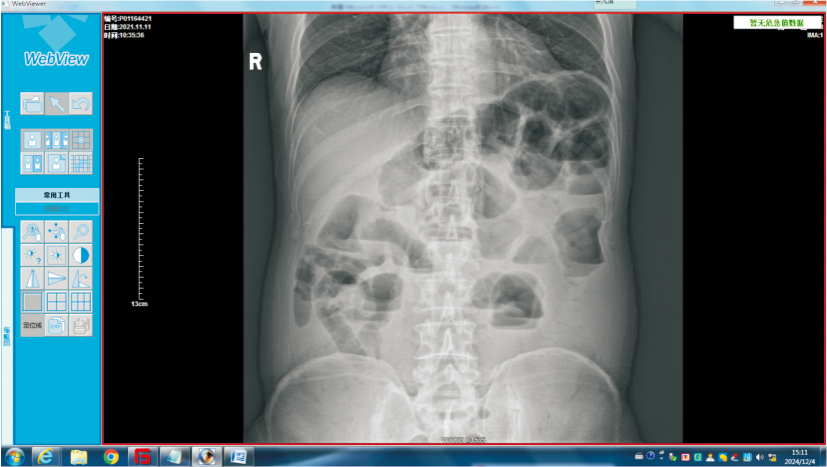

Received:2023-09-19Online:2024-11-25Published:2025-03-17Contact:ZHOU Yong E-mail:littleking1987@sina.cnFig 2

Comparison of CT findings of 5 and 15 days after insertion of transnasal ileus catheter A: 5 d after insertion of transnasal ileus catheter, the signs of multiple soft tissue density in abdominal cavity, suggesting the incomplete low small intestinal obstruction; B: 15 d after insertion of transnasal ileus catheter(similar level), multiple soft tissue density in abdominal cavity, and fluid accumulation and dilation in ascending colon.